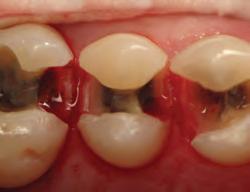

• Large food trap above

• Fails to restore proximal anatomy

• Thin contact at the marginal ridge

• Likelihood of fracture, occlusal interference, recurrent caries, and periodontal disease

• User-friendly system

• Natural contours

• Tight, anatomically correct contact points at correct height of contour

DISTO-OCCLUSAL CLINICAL CASE